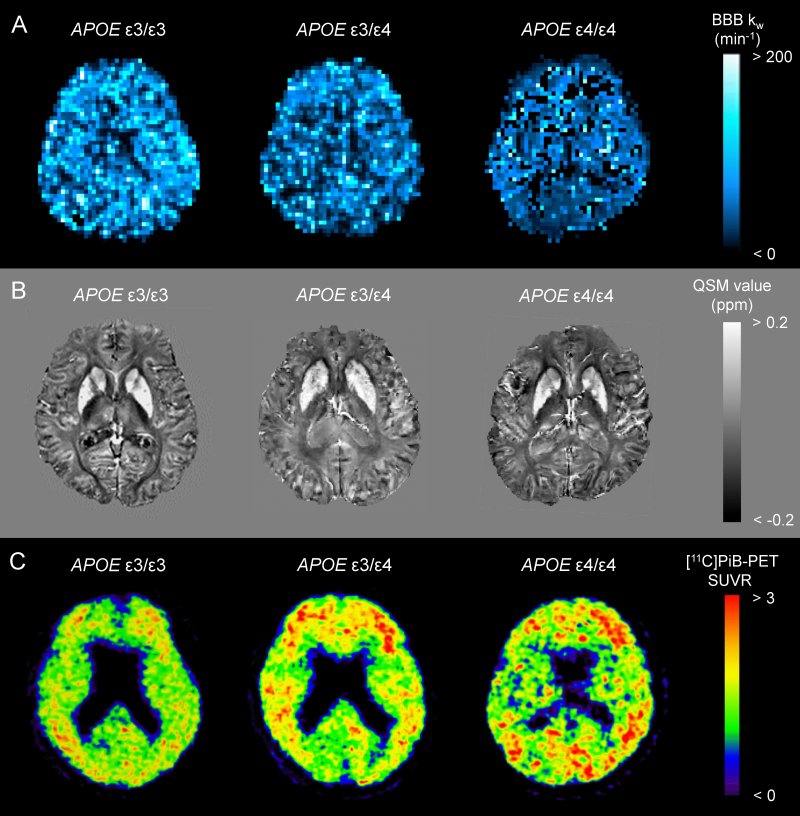

Mappa dell'indice kw (scambio acqua) della barriera emato-encefalica (A), QSM (B) e scsansione PET con [11c]PiB (C) di un paziente non portatore di ApoEε4 (ε3/ε3), di un eterozigota (ε3/ε4) e di un omozigota (ε4/ε).

"Poi abbiamo confrontato i biomarcatori di scansione correlati al MA, tra cui la mappa kw della BBB, la mappatura quantitativa di suscettibilità (QSM), la tomografia a emissione di positrone con il composto [11C]Pittsburgh e lo spessore corticale.

"Abbiamo concluso che la dose di ApoEɛ4 è associata a una scarsa eliminazione dei rifiuti cerebrali attraverso la BBB, che causa l'accumulo di ferro cerebrale e Aβ".